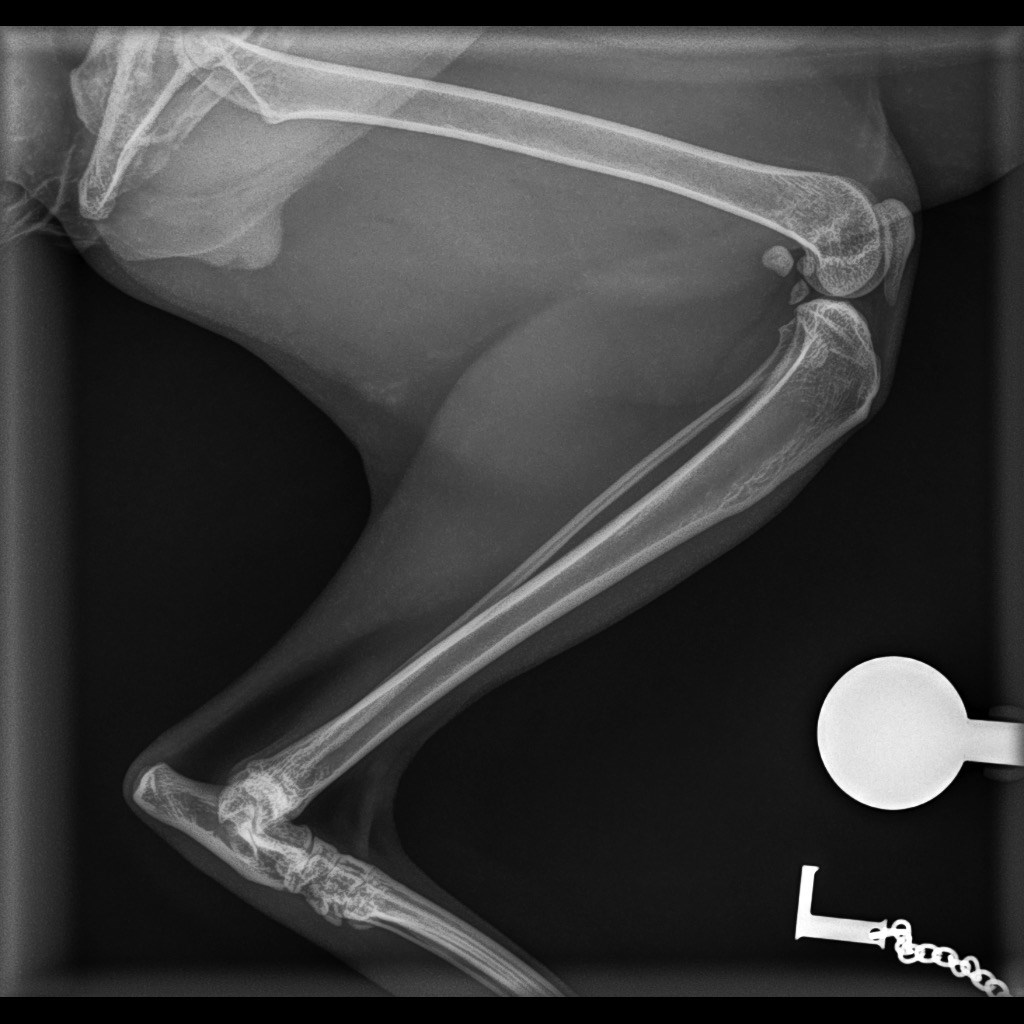

Onze lieve kater Moosje is ongelukkig gevallen en heeft zijn rechterachterpootje zo ernstig beschadigd dat een operatie onvermijdelijk is. De dierenarts adviseert een pootamputatie om hem verder leed te besparen. Na veel overleg en second opinions hebben we besloten om Moos te helpen. Ook omdat volgens meerdere artsen een kat met drie poten nog een gelukkig leven kan leiden en na een aanpassingsperiode er prima mee kan omgaan. Moosje is pas 4 jaar oud en kan hopelijk nog een aantal jaren gaan genieten van alle liefde en aandacht!